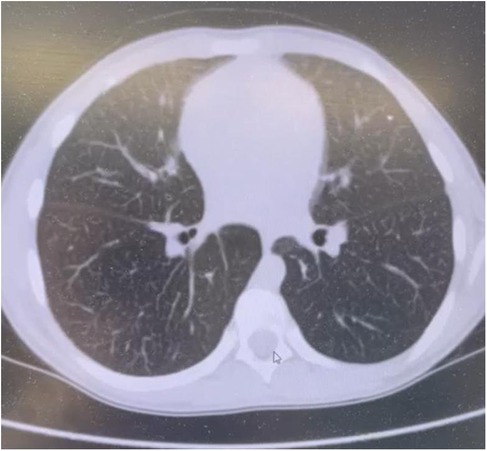

Chest computed tomography (CT) scans identified diffuse interstitial lung changes characterized by linear, reticular, and focal patterns (Figure 2).

Figure 2. Chest CT scan of a patient with acid sphingomyelinase deficiency (ASMD) type A/B disease.

Chest CT Scan Findings (Figure 2): Multiple linear and polygonal structures measuring up to 1–1.5 mm are observed throughout all lung fields, corresponding to irregularly thickened interlobular septa. The intralobular septa demonstrate a delicate, fine mesh-like thickening. The interstitium surrounding the vessels and bronchi exhibits mild, uneven wall thickening. Numerous small, well-defined centrilobular nodules are present in all lung zones. No evidence of acute infiltrative lung changes is noted. Pulmonary aeration is preserved without compromise. There is mild diffuse distortion of the bronchovascular architecture. Intrathoracic lymphadenopathy is characterized by multiple small paratracheal and mediastinal lymph nodes measuring up to 4 mm, alongside solitary bronchopulmonary lymph nodes measuring 11 mm on the right and 8 mm on the left. No pleural effusion is identified.